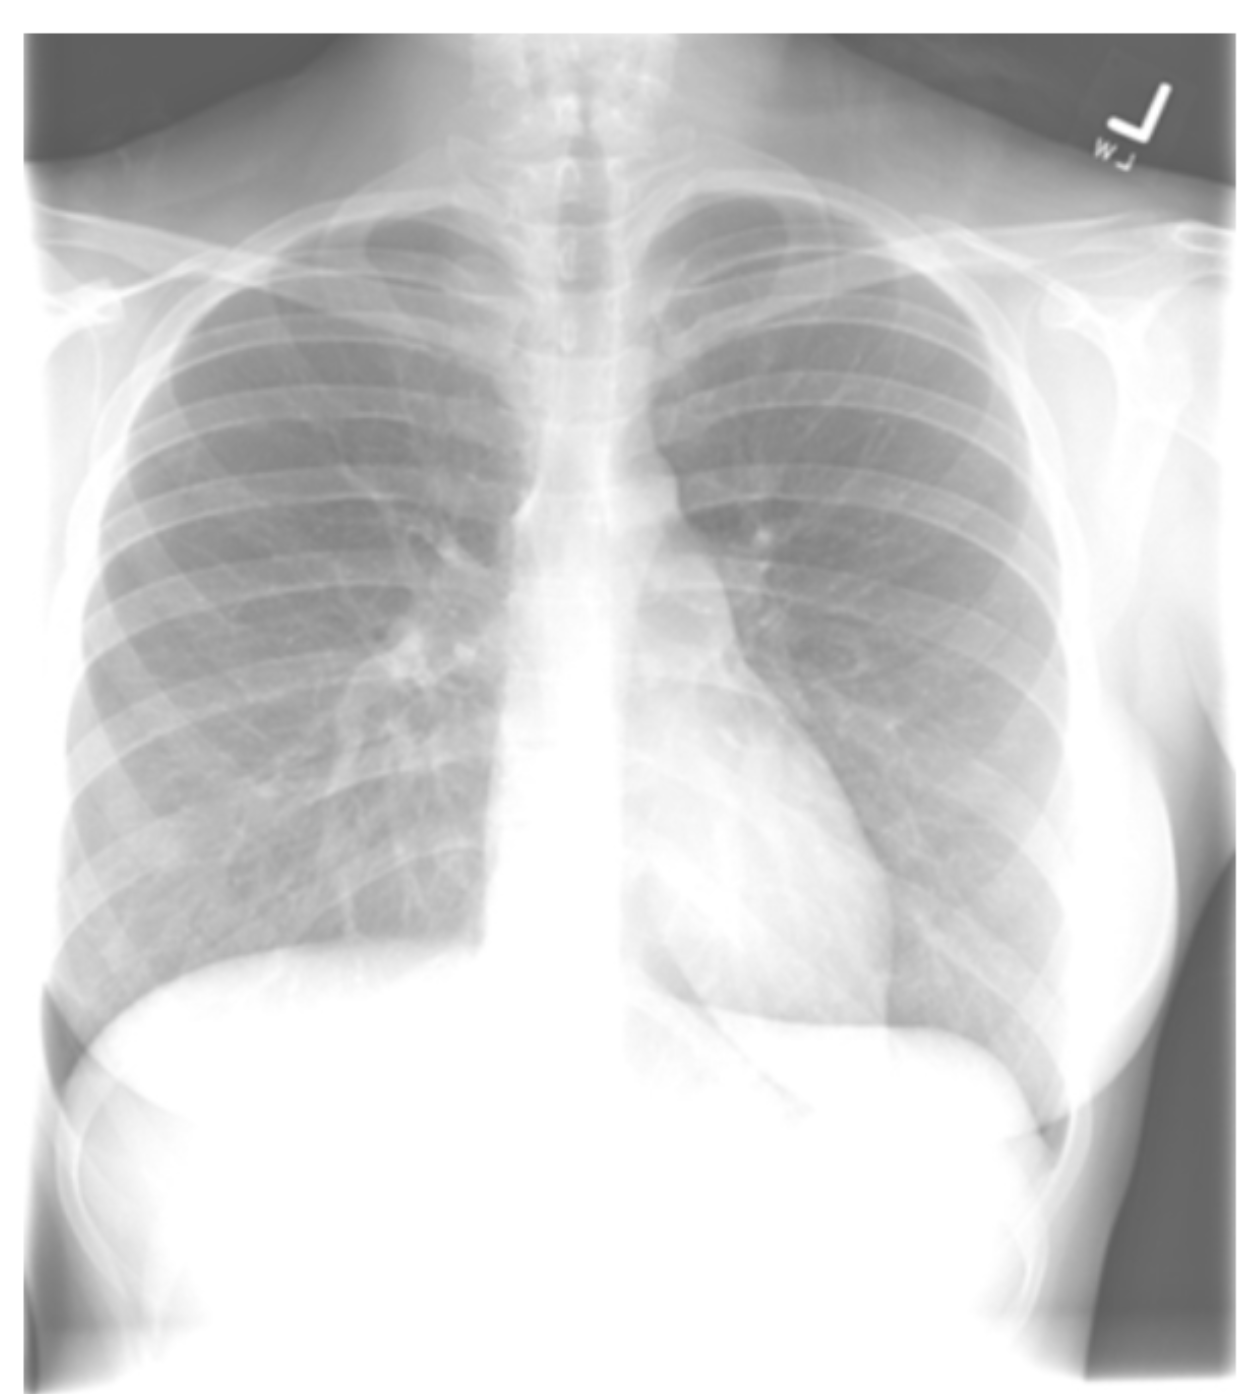

A 37-year-old woman presents to her outpatient provider for evaluation of dull chest pain for the past two months. The pain is more profound in the right chest and worsens with physical activity. A chest radiograph is obtained as part of the work-up and shown below. What qualities best describe the characteristics of this image?

The quality of a chest x-ray is determined based on a combination of penetration, inspiratory effort, and rotation. Technical view describes whether an image is taken via an AP or PA approach. A chest x-ray was appropriately obtained in the workup of this patient’s symptoms. The above image demonstrates adequate inspiratory effort, underpenetration, and midline alignment. When reviewing a chest x-ray, it is important to assess its quality and technical view, which describes whether an image is taken anterior-posterior (AP) or posterior-anterior (PA). Quality is based on a combination of three metrics: The first metric is penetration, which describes the extent to which the x-rays have passed through the patient’s body. If a study is adequately penetrated, then the lower thoracic spine should be visualized through the cardiac shadow. If the lower thoracic spine is not visualized, the study is under-penetrated. In contrast, in an over-penetrated study, too many x-rays pass through low density structures, causing the lung fields to appear black, increasing the risk that pathologic findings are missed. The second metric is inspiration. In a film with adequate inspiratory effort, 8-10 posterior ribs can be seen above the diaphragm. The final metric is rotation, which can be determined by evaluating the relationship between the clavicles and the spine. If the medial ends of the clavicles are equidistant from the thoracic spinous process, then the patient is midline and not rotated.